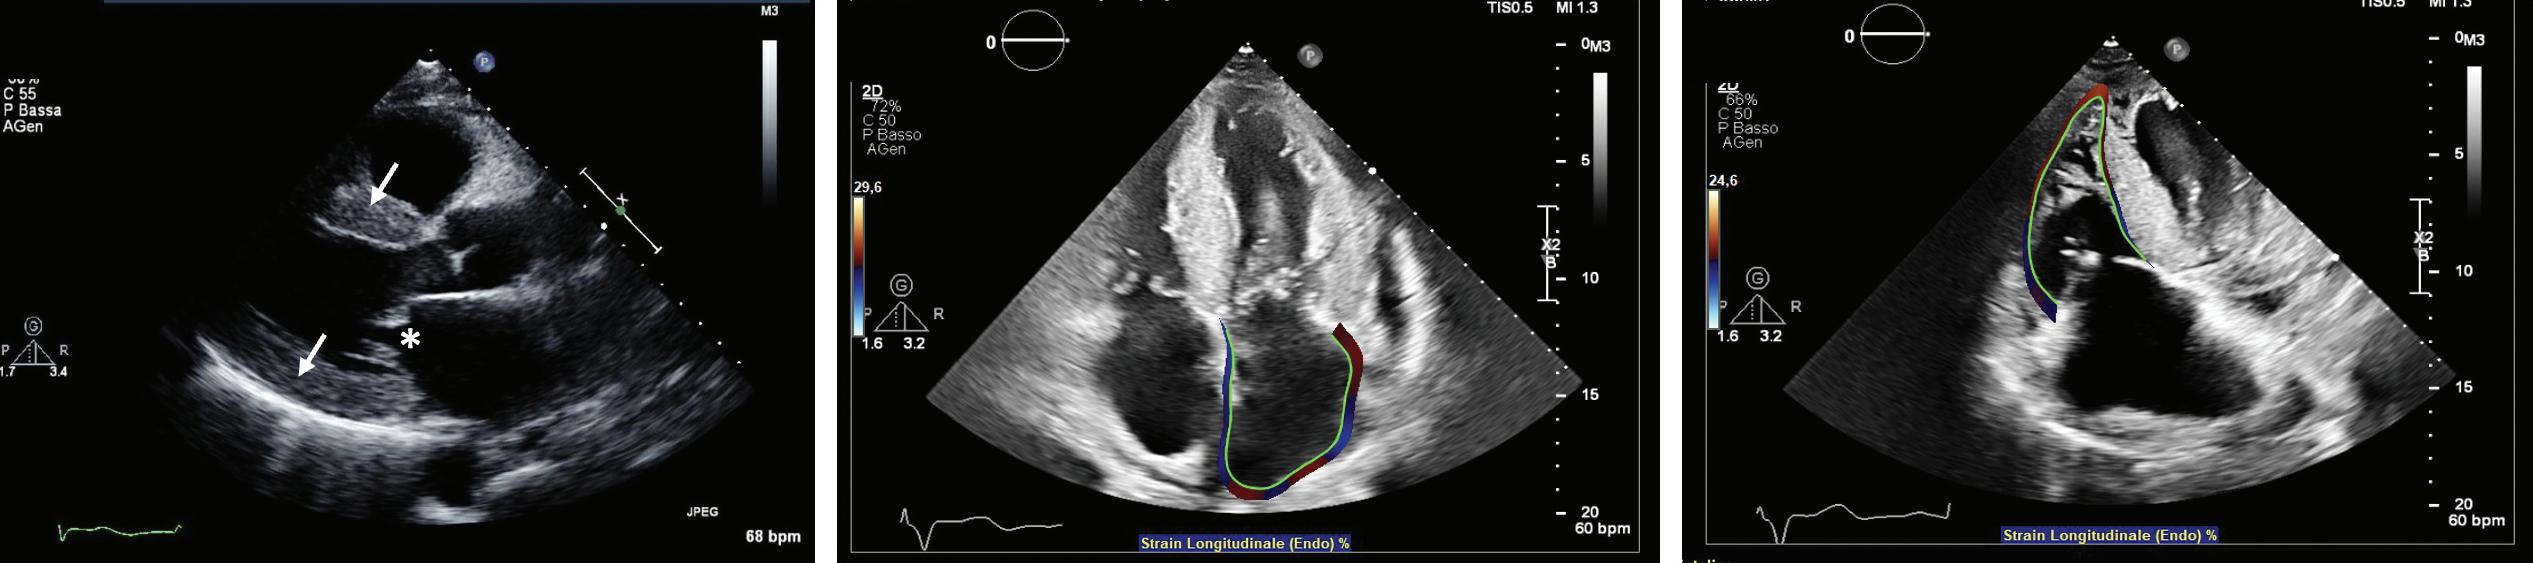

Imaging in Heart Failure with Preserved Ejection Fraction: A Multimodality Imaging Point of View

Serkan Ünlü, Özge Özden and Ahmet Çelik

Role of Imaging in Cardiomyopathies

Vincenzo Castiglione, Alberto Aimo, Giancarlo Todiere, Andrea Barison, Iacopo Fabiani, Giorgia Panichella, Dario Genovesi, Lucrezia Bonino Alberto Clemente, Filippo Cademartiri, Alberto Giannoni, Claudio Passino, Michele Emdin and Giuseppe Vergaro

DOI: https://doi.org/10.15420/cfr.2022.26